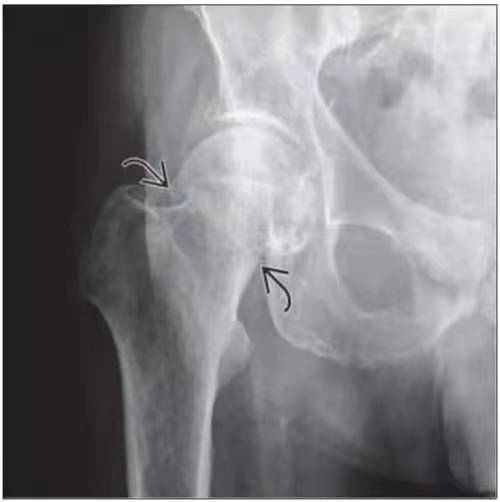

股骨頸骨折是指股骨頭下至股骨頸基底部之間的骨折,主要發(fā)生于老年人,造成老年人發(fā)生骨折有兩個(gè)基本因素,骨質(zhì)疏松骨強(qiáng)度下降,加之股骨頸上區(qū)滋養(yǎng)血管孔密布,均可使股骨頸生物力學(xué)結(jié)構(gòu)削弱,使股骨頸脆弱。另外,因老年人髖周肌群退變,反應(yīng)遲鈍,不能有效地抵消髖部有害應(yīng)力,加之髖部受到應(yīng)力較大(體重2~6倍),局部應(yīng)力復(fù)雜多變,因此不需要多大的暴力,如平地滑倒、由床上跌下或下肢突然扭轉(zhuǎn),甚至在無明顯外傷的情況下都可以發(fā)生骨折。而青壯年股骨頸骨折,往往由于嚴(yán)重?fù)p傷如車禍或高處跌落致傷。